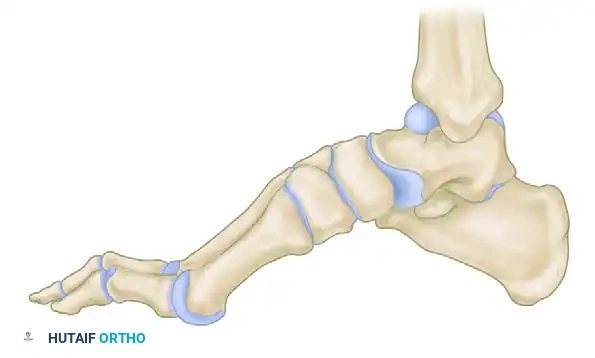

Postoperative lateral skeletal representation demonstrating a restored, plantigrade alignment following successful closing wedge osteotomies.